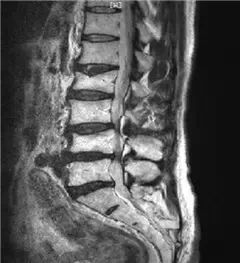

腰椎MRI L3-4、L4-5